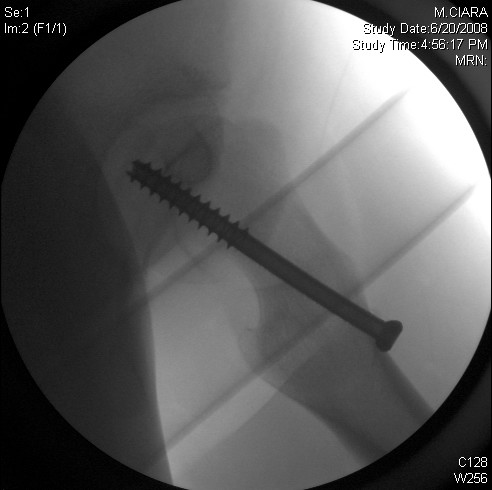

Screw fixation radiograph

Screw fixation — radiograph.